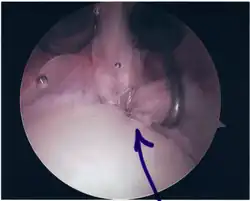

Twelve varieties of SLAP lesion have been described, with initial diagnosis by MRI or arthrography and confirmation by direct arthroscopy.[9]

Surgical treatment of SLAP tears has become more common in recent years. The success rate for repairing isolated SLAP tears is reported between 74-94%.[10] While surgery can be performed as a traditional open procedure, an arthroscopic technique[11] is currently favored being less intrusive with low chance of iatrogenic infection.[12]

Following inspection and determination of the extent of injury, the basic labrum repair is as follows.

- The glenoid and labrum are roughened to increase contact surface area and promote re-growth.

- Locations for the bone anchors are selected based on number and severity of tear. A severe tear involving both SLAP and Bankart lesions may require seven anchors. Simple tears may only require one.

- The glenoid is drilled for the anchor implantation.

- Anchors are inserted in the glenoid.

- The suture component of the implant is tied through the labrum and knotted such that the labrum is in tight contact with the glenoid surface.